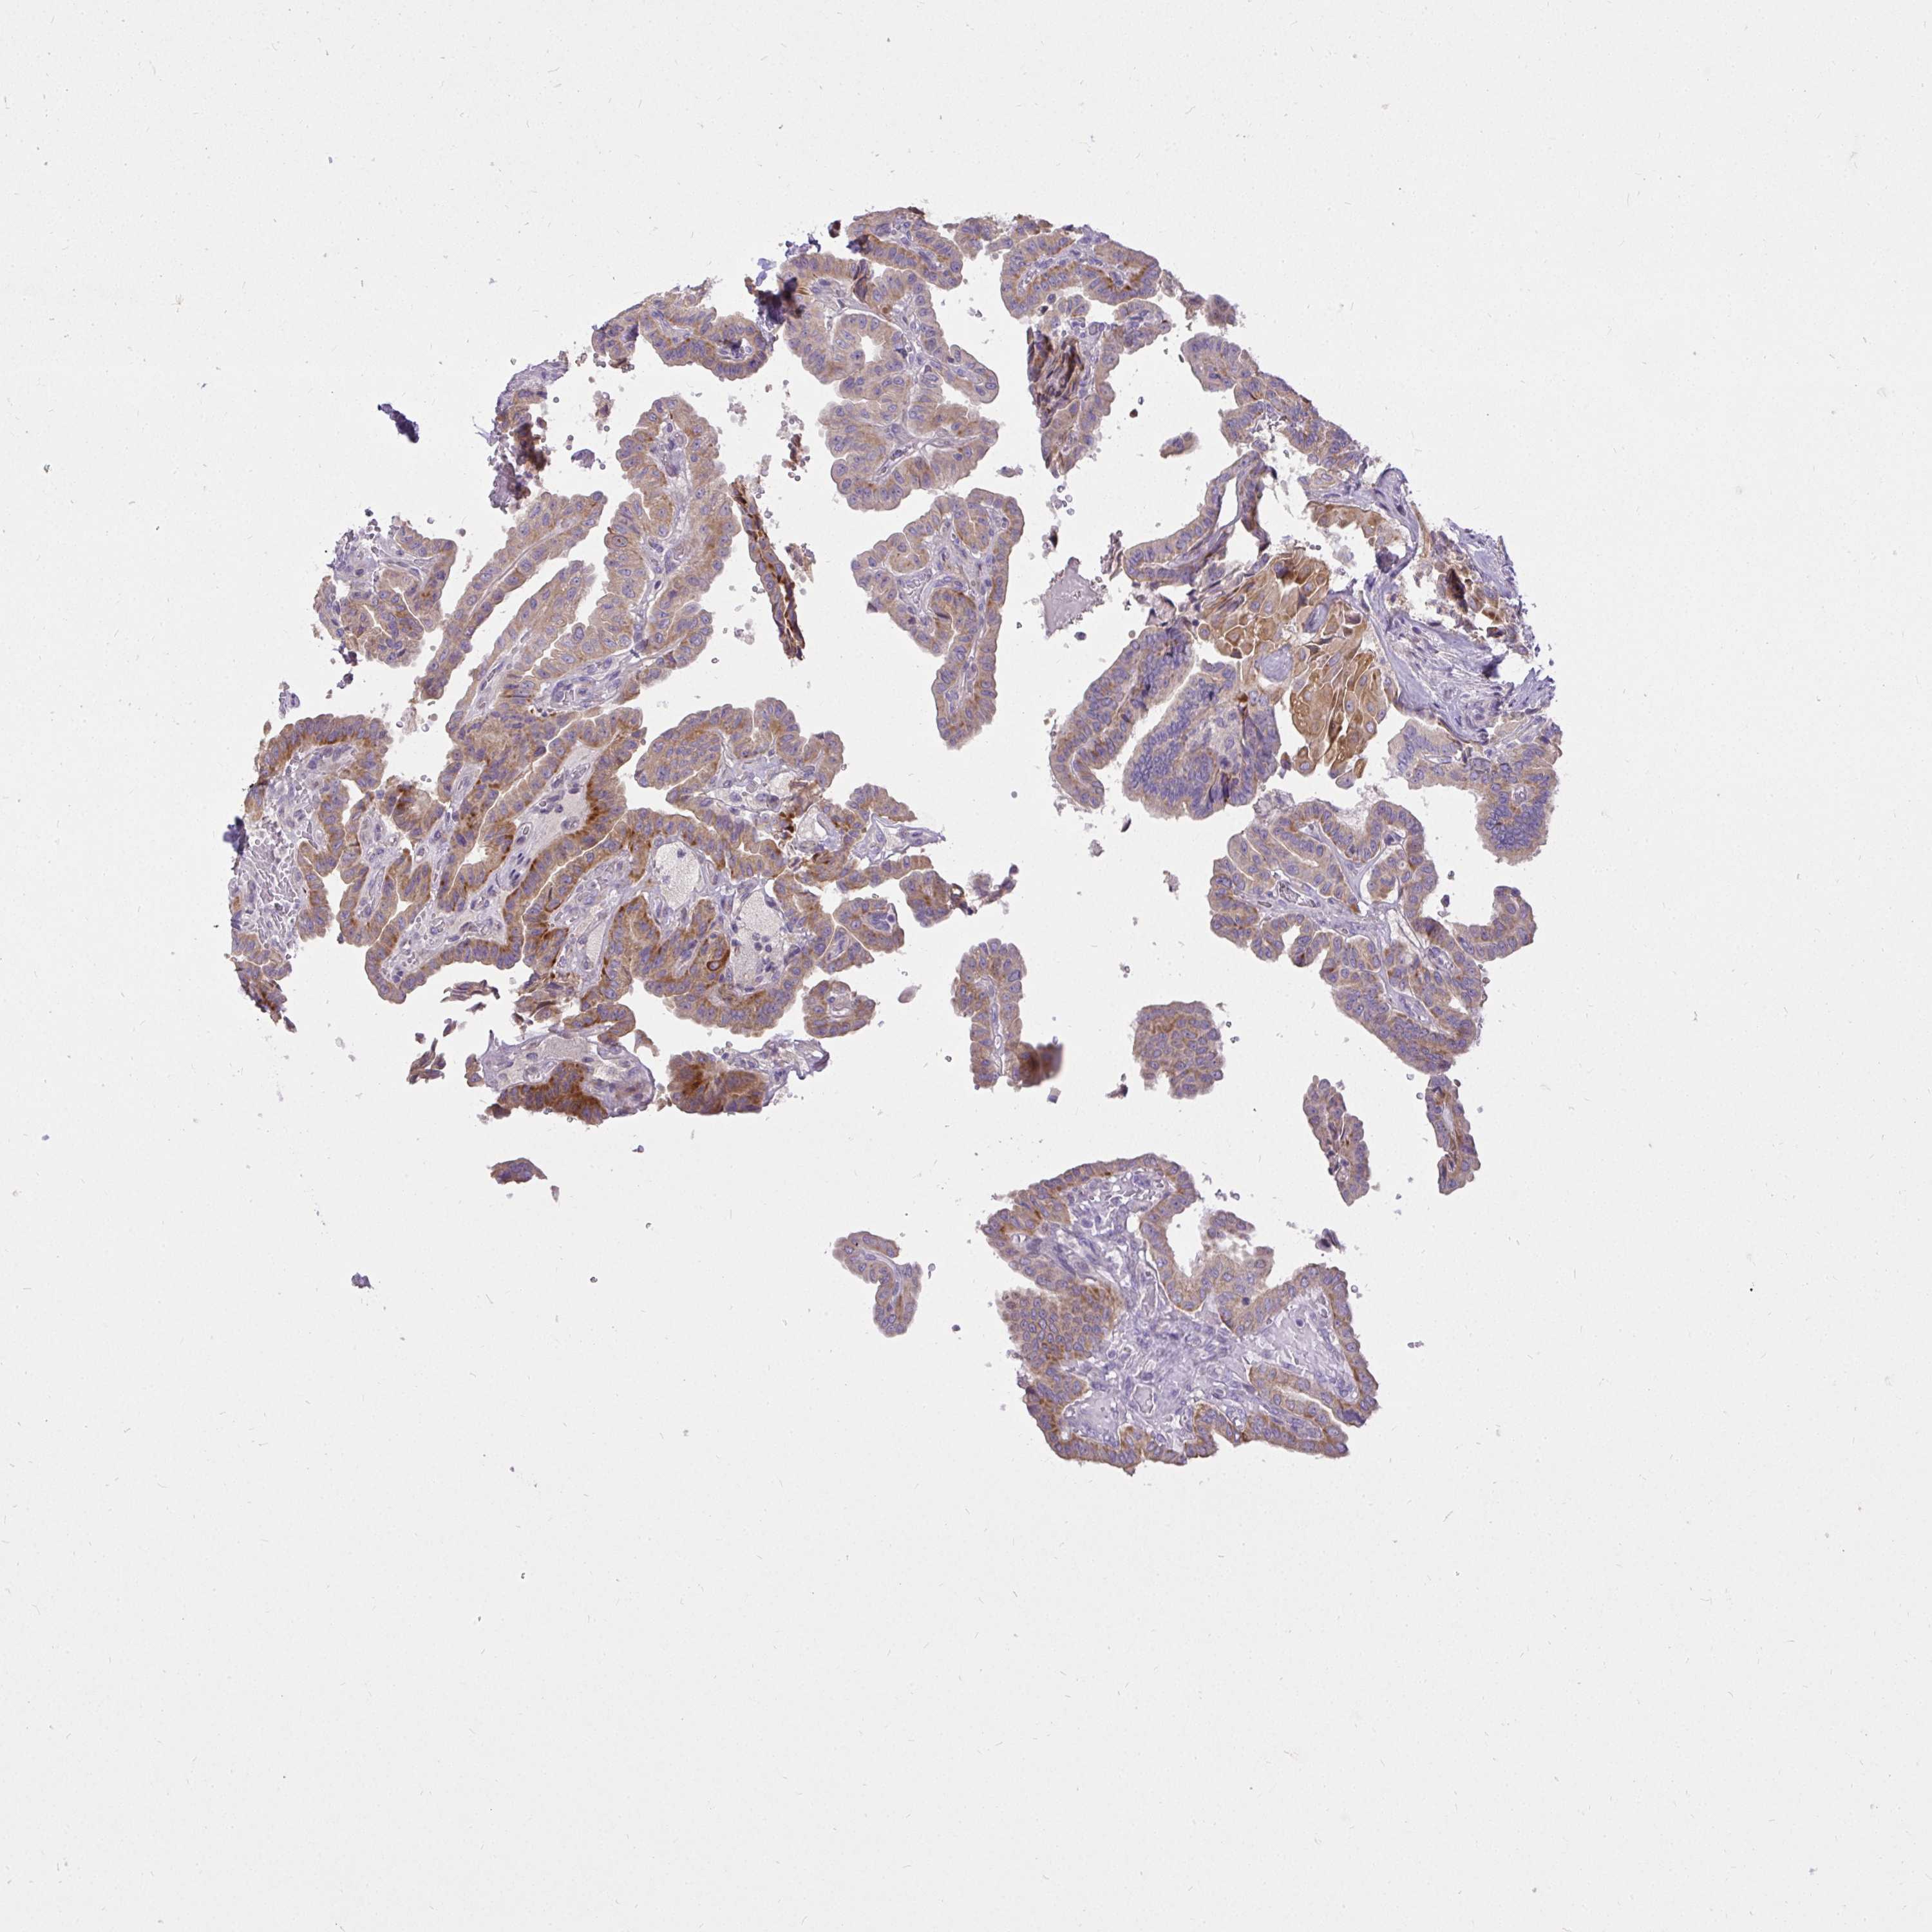

THYROID CANCER - Protein expressioni

A mouse-over function shows sample information and annotation data. Click on an image to view it in a full screen mode. Samples can be filtered based on level of antibody staining by selecting one or several of the following categories: high, medium, low and not detected. The assay and annotation is described here.

Note that samples used for immunohistochemistry by the Human Protein Atlas do not correspond to samples in the TCGA dataset.

Antibody stainingi

Antibody staining in the annotated cell types in the current human tissue is reported as not detected, low, medium, or high, based on conventional immunohistochemistry profiling in selected tissues. This score is based on the combination of the staining intensity and fraction of stained cells.

Each image is clickable and will lead to virtual microscopy that enables deeper exploration of all samples and also displays staining intensity scores, fraction scores and subcellular localization as well as patient and tissue information for each sample.

Antibody HPA060302

Staining

High

Medium

Low

Not detected

Intensity

Strong

Moderate

Weak

Negative

Quantity

>75%

75%-25%

<25%

None

Location

Nuclear

Cytoplasmic/membranous

Cytoplasmic/membranous,nuclear

Papillary adenocarcinoma, NOS

Follicular adenoma carcinoma, NOS